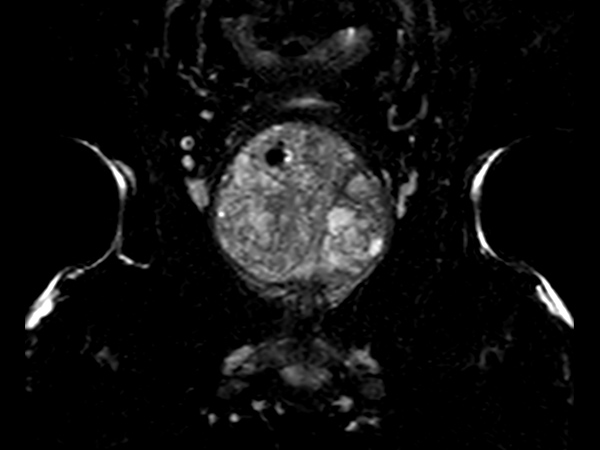

Multi-phase, contrast-enhanced prostate imaging

Patient with a prostate lesion. The ExamCard includes techniques for 3D imaging (PelvisVIEW, eTHRIVE) allowing for multiple image directions in one single scan, efficient fat-free imaging over large field-of-views (mDIXON XD), a multi-phase contrast-enhanced sequence (4D FreeBreathing) to improve imaging confidence and Compressed SENSE to accelerate the entire exam.